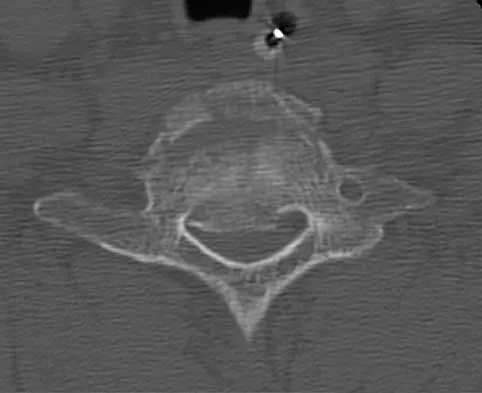

Figures 8a through 8d show the radiographs and CT scans of a 14-year-old girl who has a painful, rigid planovalgus foot. Management consisting of arch supports and anti-inflammatory drugs failed to provide relief. A below-knee walking cast resulted in pain resolution, but she now reports that the pain has recurred. Management should now consist of

Explanation